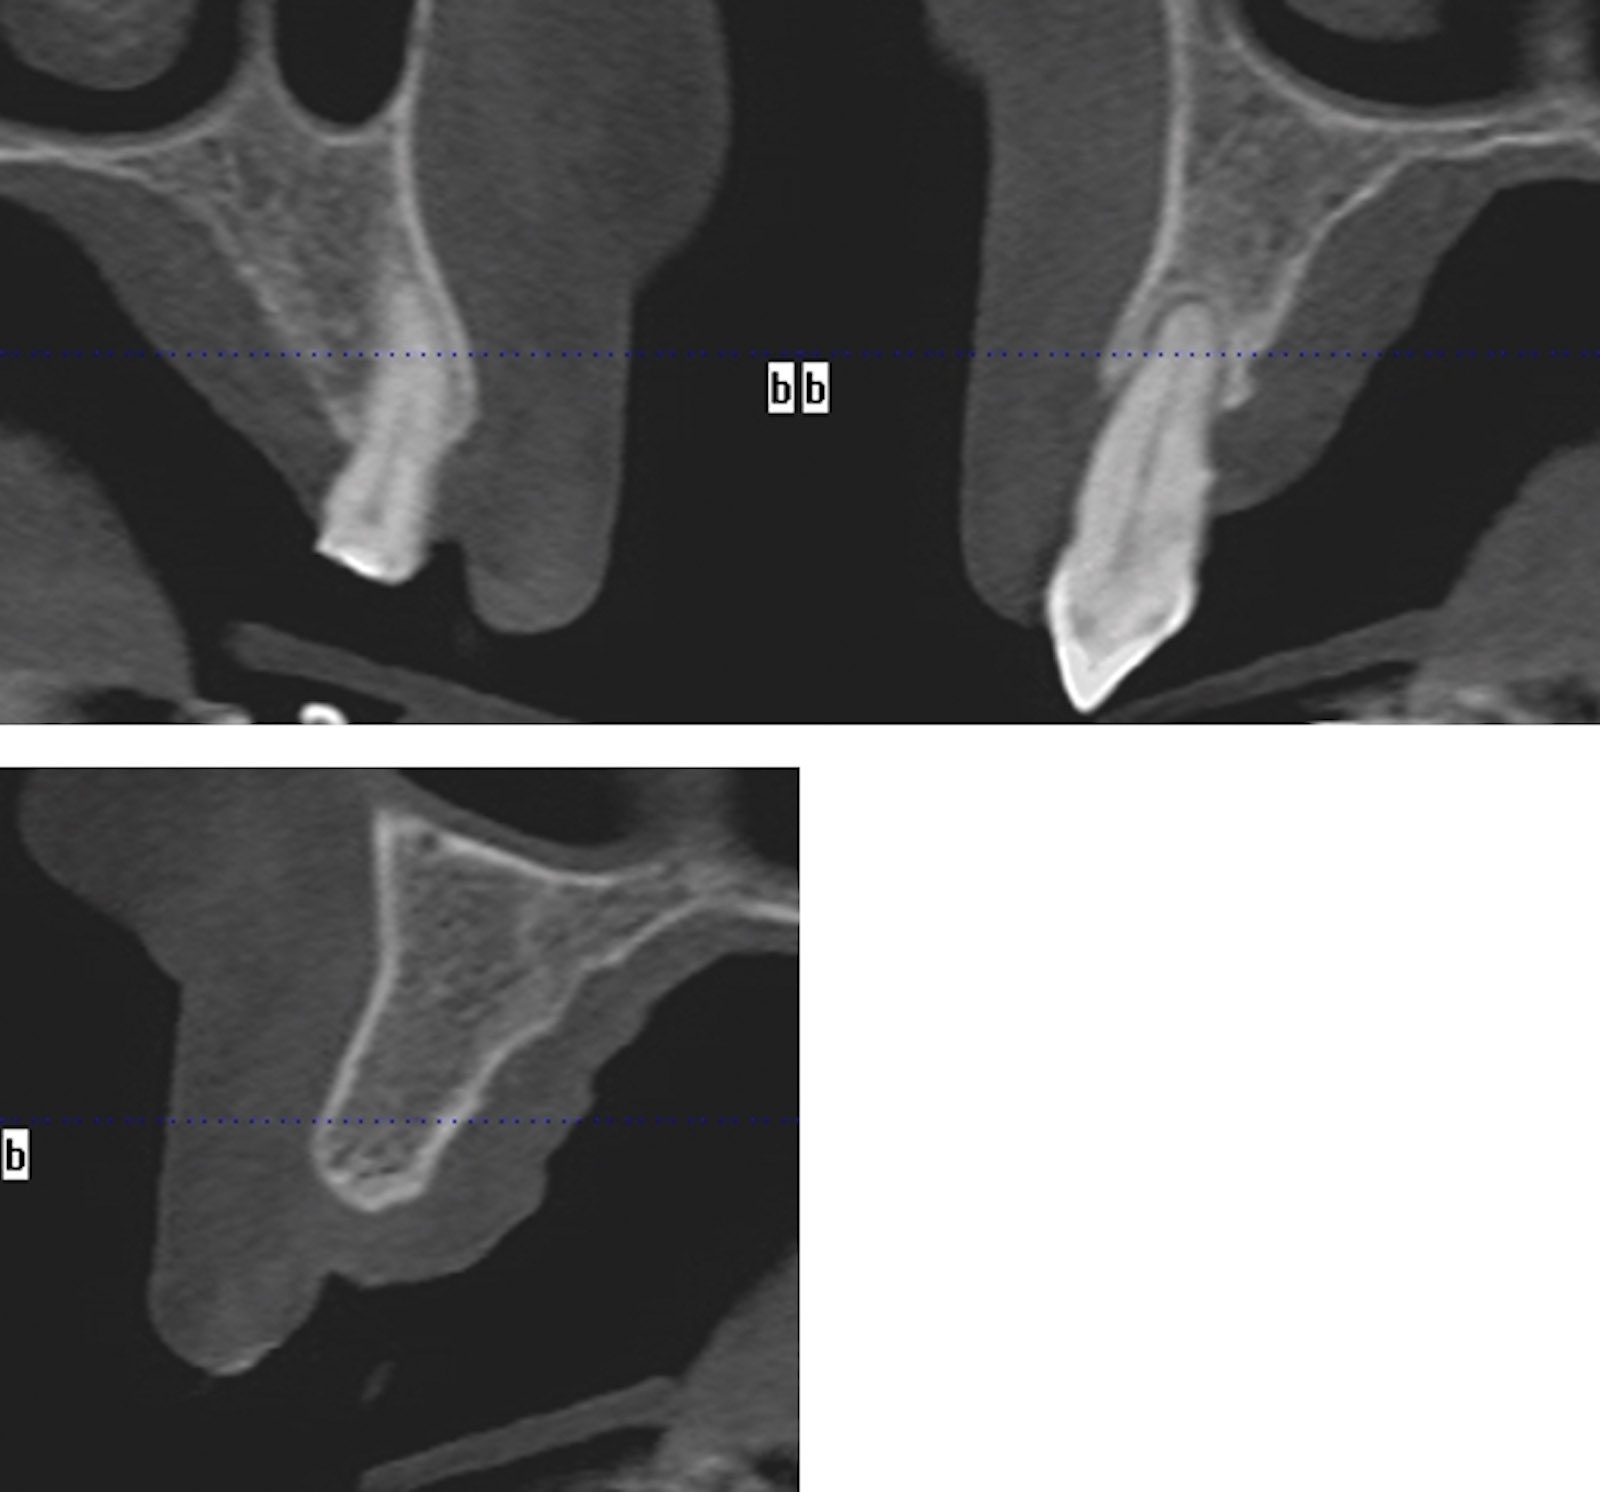

A CBCT scan of the upper jaw was taken to accurately assess the anatomy of the maxilla, the trajectory of the alveolar ridges and to ascertain if immediate implant placement was going to be possible (Figures 4). The scan confirmed adequate bone volume in the anterior maxilla, with good bone height beyond the apices of the failing teeth and intact labial alveolar plates, the density of the trabecular bone was adequate to allow for very good initial primary stability for the immediate placement and loading of the implants. The CBCT scan also confirmed inadequate bone volume beneath the maxillary sinuses (Figure 5).